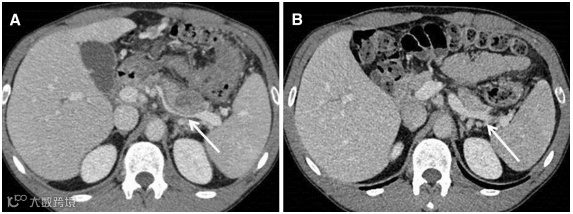

(图源自文献)

A,一例41岁男性病因不明的坏死性胰腺炎患者,轴位CT显示:胰尾部坏死组织(箭头)的直接压迫导致其远端部分脾静脉血栓形成。该病例证实了血栓形成的发病机制与局部组织炎症或直接压迫有关。

B,脾静脉血栓和胰腺坏死组织积聚消失(箭头)。